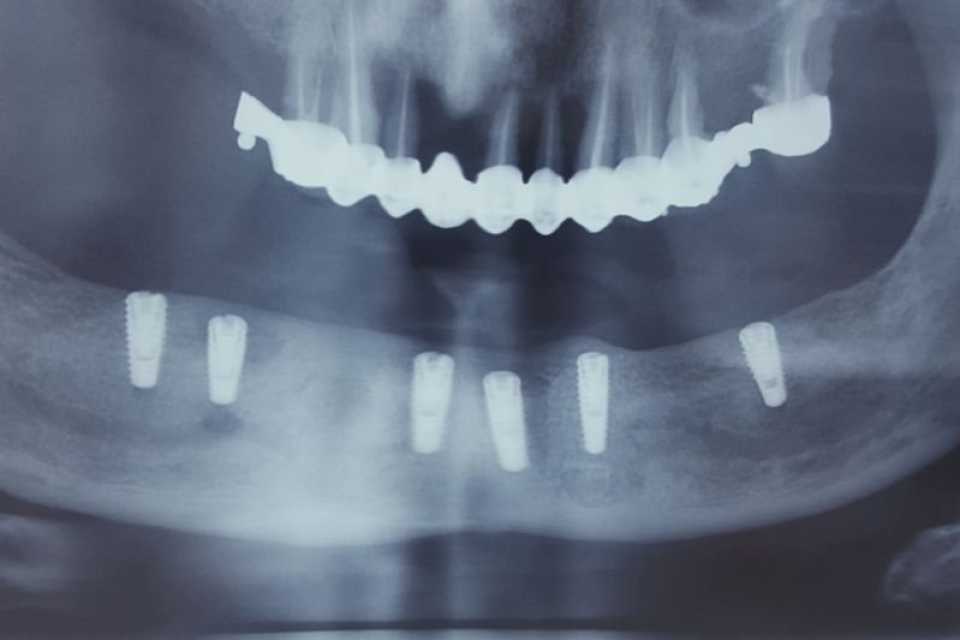

Cazul 36: All on X

Pacientul, în vârstă de 67 de ani, s-a prezentat la cabinet din motive estetice și funcționale.

Împreună cu pacientul am optat pentru o protezare fixa pe implanturi. Reabilitarea a fost efectuată cu ajutorul unei lucrari fixe (12 elemente metalice-ceramice, 500 lei/element) stabilizat prin montarea pe 6 implanturi dentare (Megagen, preț 400 euro/implant).